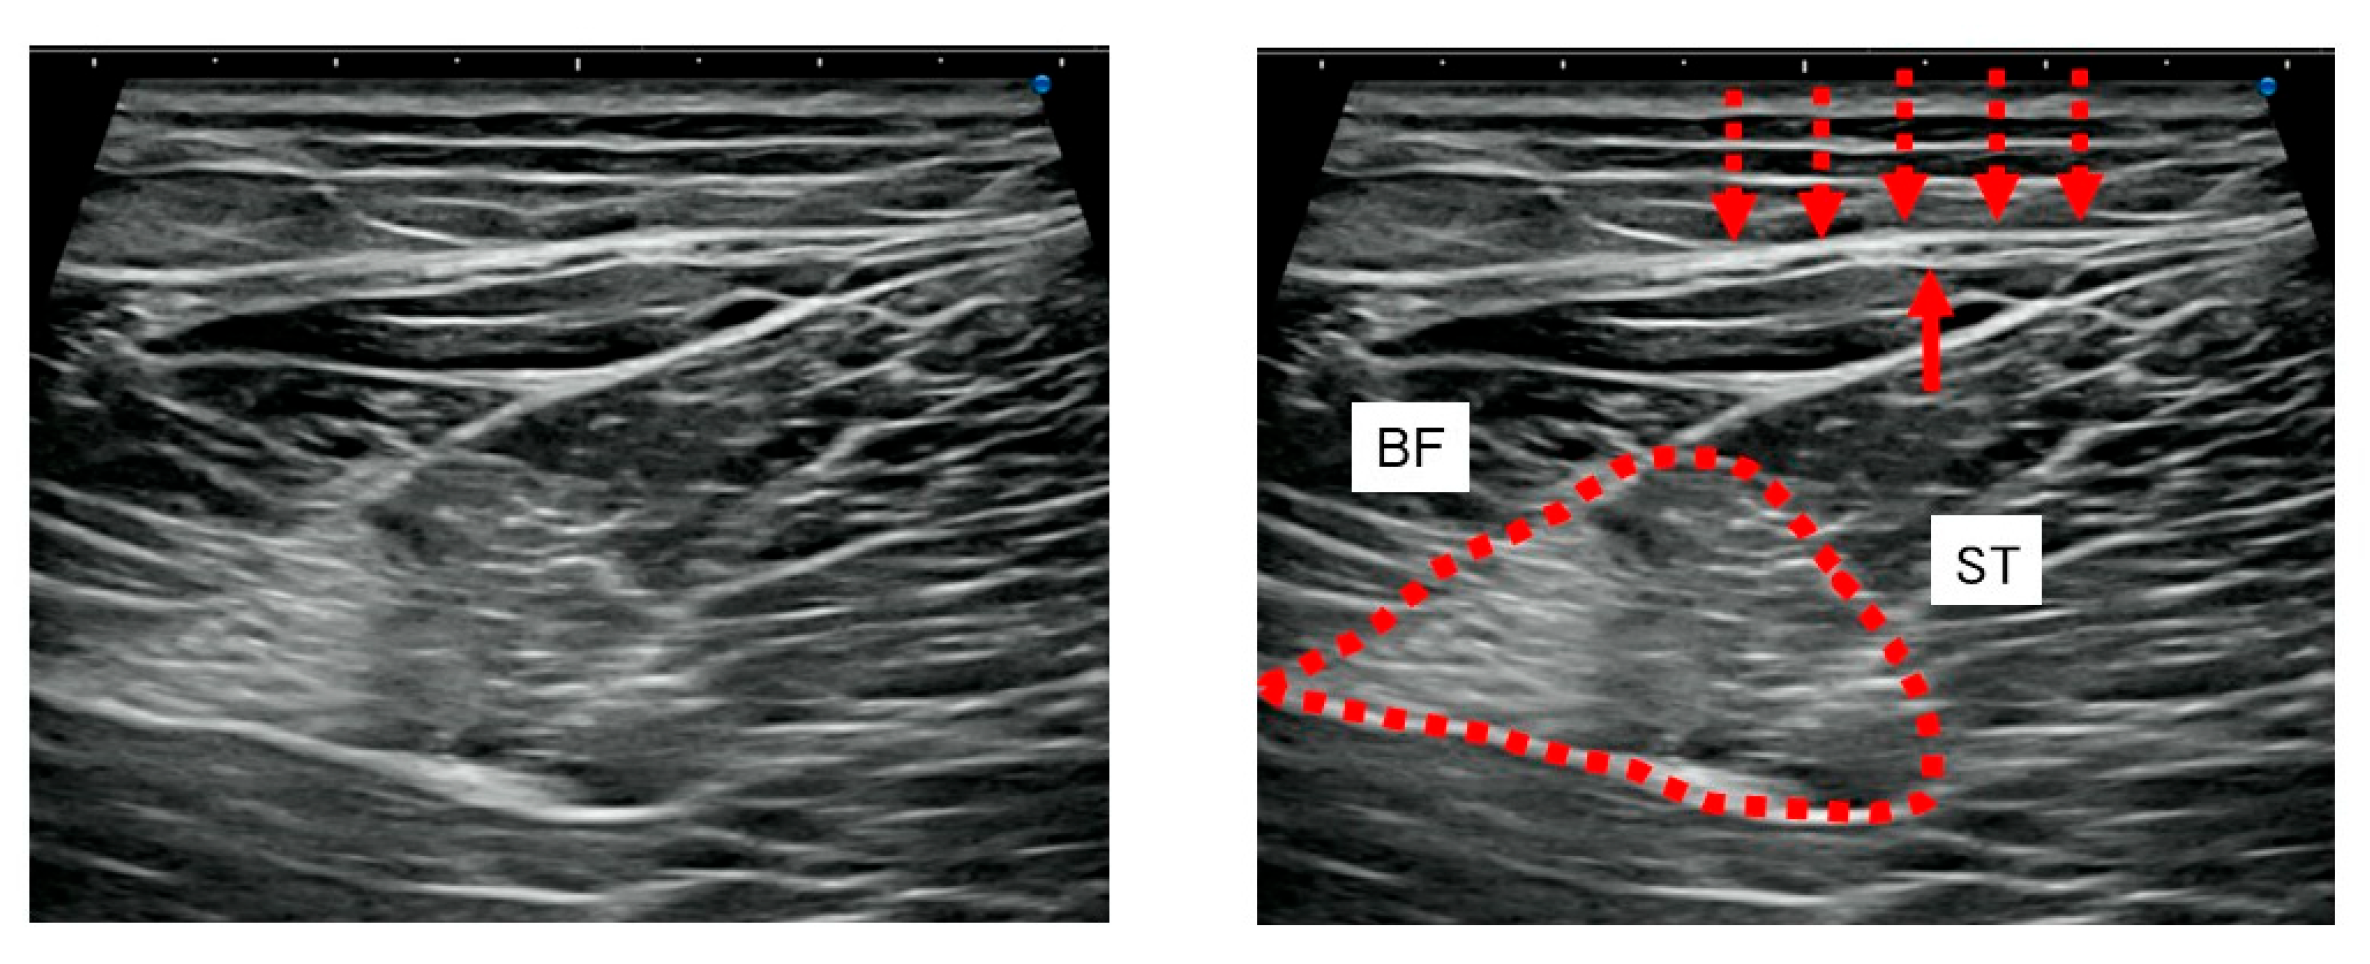

2.4. US Imaging and Sonopalpation

3.3. US Imaging and Sonopalpation